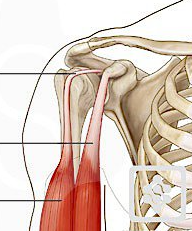

What is the superior tendon (highest point) shown here?

Tendon of the long head of the biceps brachii muscle.